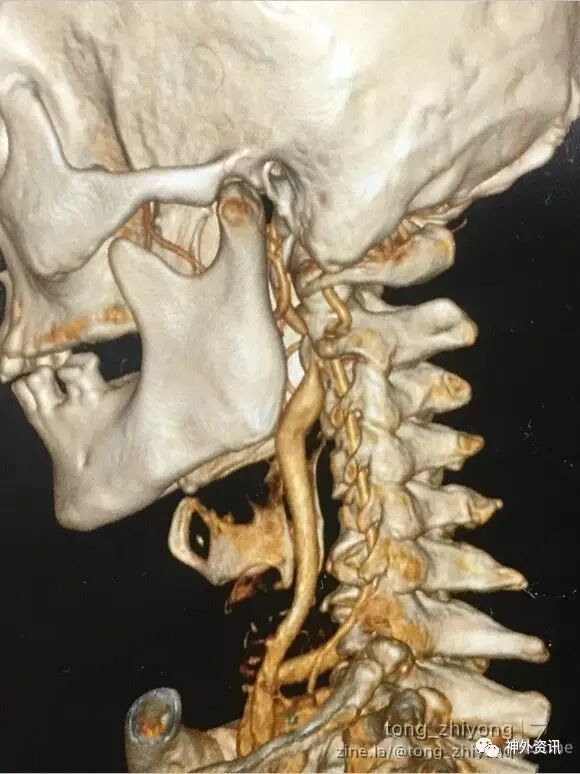

老年,男性,症状性左侧颈动脉重度狭窄

左侧颈内动脉高位狭窄:狭窄位于C2椎体水平,下颌角后上方

狭窄部位局限,颈内动脉稍迂曲

术中血管造影显示:颈动脉通畅,管径增宽,迂曲解除